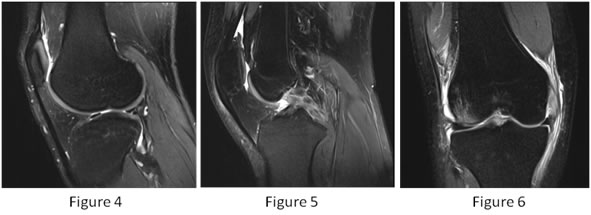

Figure 4: Sagittal T2 Fat suppressed MR image shows oblique tear of lateral meniscus involving posterior horn.

Figure 5: Sagittal T2 Fat suppressed MR image shows loss of continuity of PCL fibres with wavy contour and abnormal signal within – Complete PCL tear.

Figure 6: Coronal PD Fat suppressed MR image shows bone contusion in medial femoral condyle with joint effusion.